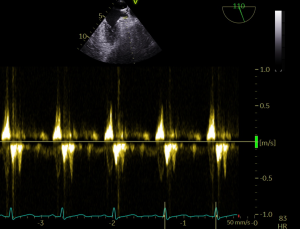

PLAX M Mode is shown below. Cursor line is placed through the aortic valve. Findings are consistent with